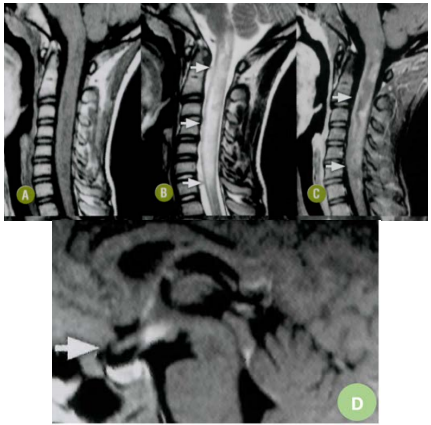

Uma paciente de 26 anos procura o pronto atendimento com queixa de dificuldade visual, seguida de perda de força nos 4 membros e dificuldade de urinar. Seu exame neurológico revelou hemianopsia heterônima, tetraparesia espástica, grau 3, hiperreflexia, hipoestesia com nível cervical para todas as formas e bexigoma. O líquor da paciente apresentou aumento leve de proteína, sem outras alterações no exame de rotina. O exame de Ressonância Magnética (RM) sagital da medula espinal cervical ponderadas em T1 (A), T2 (B) e T1 póscontraste (C) demonstra extensa mielite com hipossinal em T1 e hipersinal em T2, além de impregnação heterogénea ao contraste (setas). E o comprometimento óptico quiasmático é apresentado em detalhe de corte sagital de RM cerebral em FLAIR (seta)(D).

Caso clínico elaborado pelo(a) autor(a). Imagem: Rocha AJ, Vedolin L e Mendonça RA. Encéfalo. Rio de Janeiro. Elsevier, 2012: 657-658. 1.